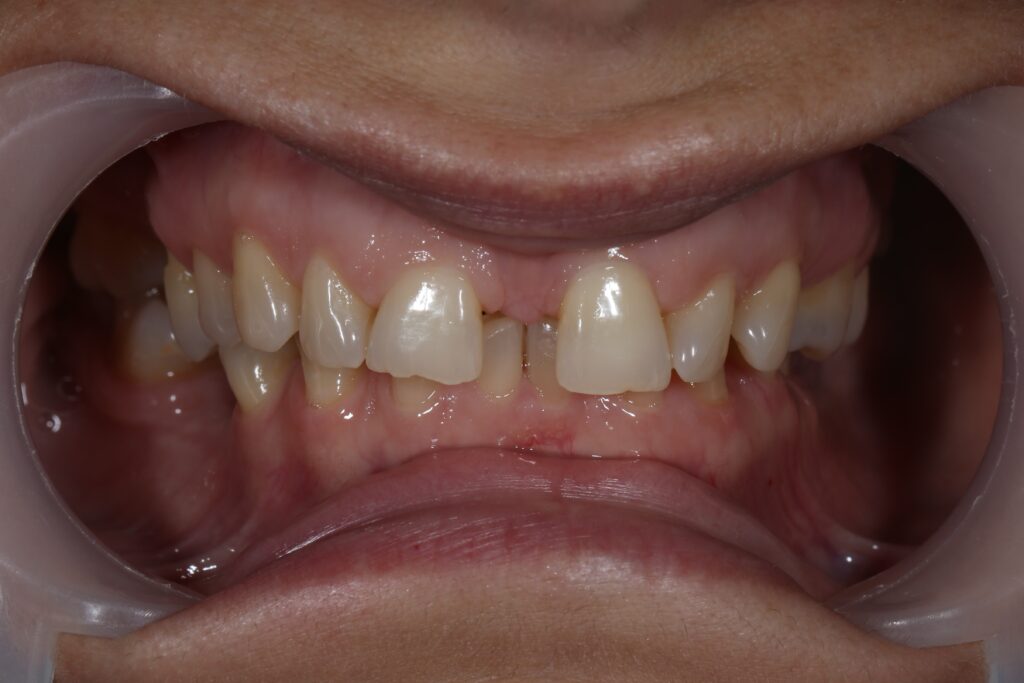

Ситуация до лечения

Пациентка 39 лет была направлена стоматологом-ортопедом для ортодонтической подготовки перед протезированием.

Из-за множественных давних удалений жевательных зубов, произошла деформация зубных рядов, зубы разъехались в область удаленных, что затрудняло протезирование в момент обращения к ортопеду.

Так же можно отметить сильное снижение высоты прикуса (верхние зубы на 100% перекрывали нижние, что вызывало хроническую травму десны), а также повышенную стираемость твердых тканей зубов,

что является следствием повышенной нагрузки, которую много лет испытывали передние зубы, в связи с отсутствием жевательных зубов.

пациент до брекетов